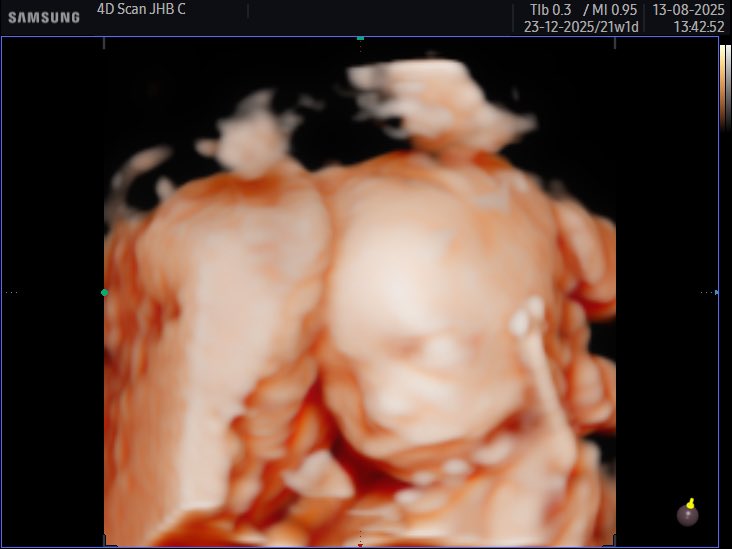

Super surreal 🥺🥰 the way this little girl kicks already, she might be a little athlete but the mouse will be going in her hand if I can help it 🤭

Little bean 🫘 due 23rd December ✨ got lucky and baby woke up during the sonar and wiggled around for us

Cjay tweet mediaCjay tweet mediaCjay tweet media